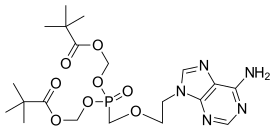

Adefovir dipivoxil contains two pivaloyloxymethyl units, making it a prodrug form of adefovir.

A prodrug form of adefovir was previously called bis-POM PMEA, with trade names Preveon and Hepsera. It can be formulated as the pivoxil prodrug adefovir dipivoxil.